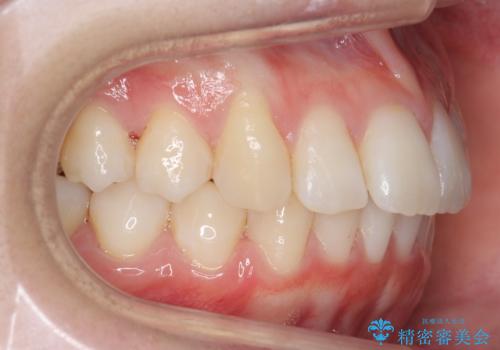

歯を抜かないで出っ歯を治したい

- 前歯が出ていることを主訴に来院。

歯を抜かずにマウスピース矯正をご希望でした。

歯と歯の間をわずかに削り、歯並びを少し横に拡大して並べました。

奥にすき間がなかったため後ろには下げていません。

沢山ひっこめるには4本抜歯でワイヤーの選択肢もありましたが、抜かないでできる範囲をご希望されました。

とがった形の歯列を整えるだけでもだいぶ印象は変わると思います。

今回歯列を広げた結果、上顎犬歯の歯肉は多少退縮しています。